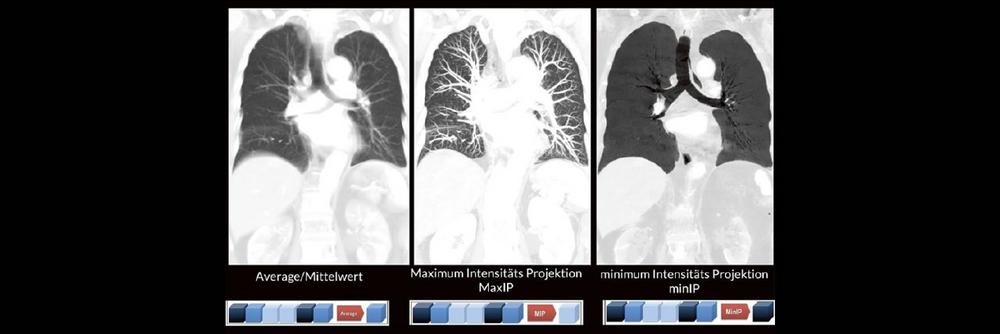

Professor Dr. med. Marc Brockmann WEITERENTWICKLUNGEN VON KOPF BIS FUSS BEIM VC Oberstarzt Dr. med. Stephan Waldeck DEEP-LEARNING-REKONSTRUKTION IN DER NEURORADIOLOGIE Die CT ist ein essentielles Routine-Verfahren in der Neuroradiologie. Bei steigender Bildqualität konnte die Röntgendosis mit neuen Technologien in der letzten Dekade deutlich gesenkt werden, was für die zielgerichtete und möglichst schonende Behandlung von…